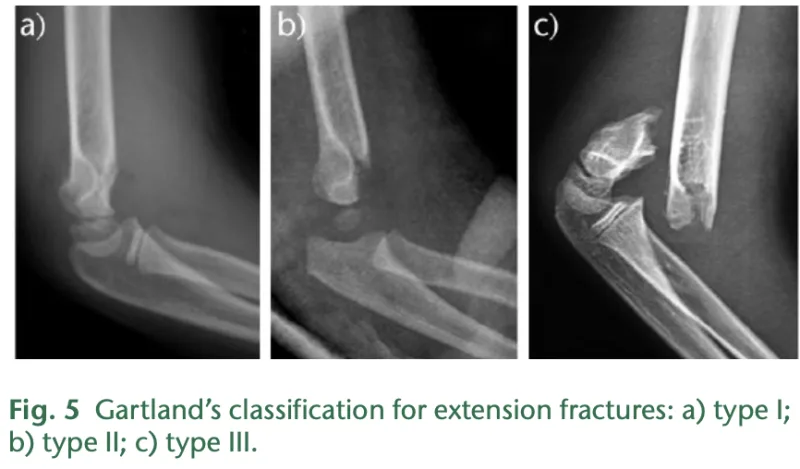

a) 転位がないtype I, b) 軽度の転位があるtype II, c) 完全に転位したtype III.

X線写真とCTを見たところ, Gartland分類type IIIで, 完全に転位した状態でした.